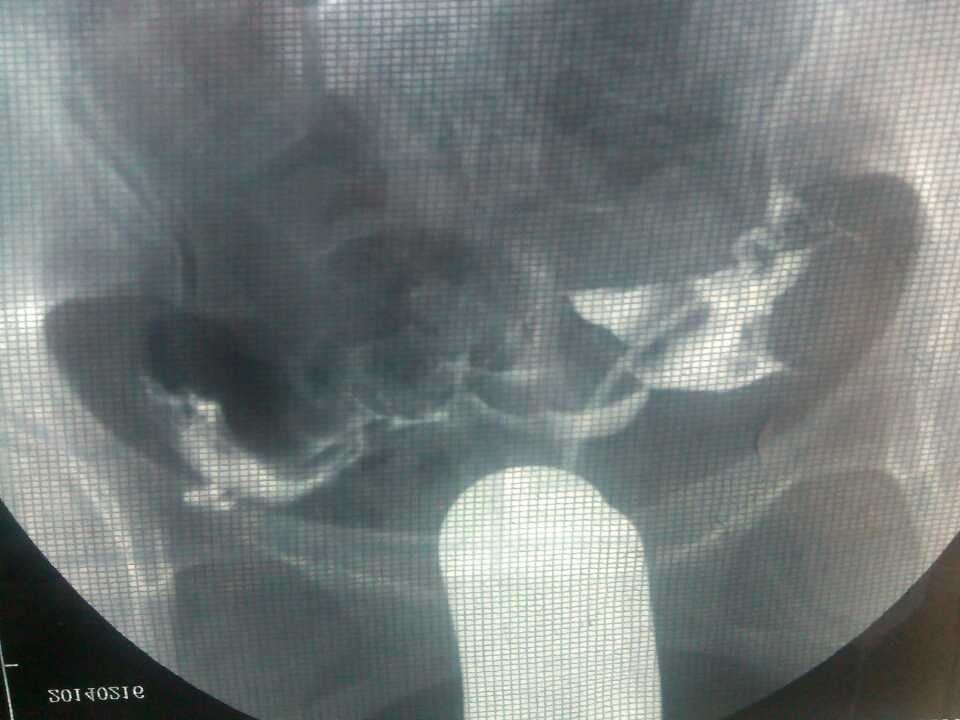

不孕 造影单子帮忙看看 点击展开 匿名用户 2014-04-10 08:51 为您推荐: 其他回答 病情分析: 你好,应该是输卵管堵塞引起的。 指导意见: 可以考虑腹腔镜手术来治疗,术后注意不可过早恢复同房,及时复查。 独水凡_xjeq 2014-04-10 10:34 相关问题 医生你们好帮忙看看我这个造影单子有木有问题 因为我备孕一年 请问医生,不孕单子上这种病情应该怎么办呢?需要手术吗? 谁帮忙看看我下面问题补充里面的检查结果?看看我能不能怀孕??有没有不孕症??